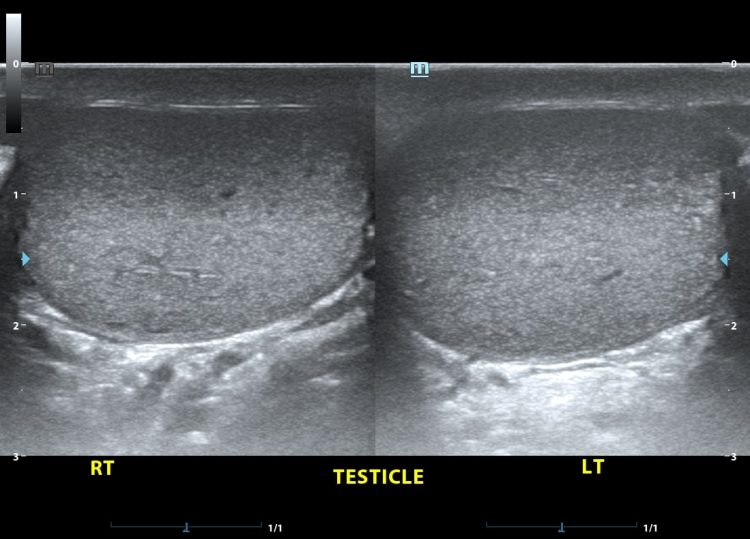

Given the increasing prevalence of testicular disorders affecting men of all ages, it is crucial to check their health. Early detection with professional imaging greatly improves treatment outcomes and survival rates for testicular cancer, one of the most frequent tumours in young men aged fifteen to thirty-five. In addition to detecting cancer, testicular scans can detect a number of painful or uncomfortable disorders, such as epididymitis, varicoceles, hydroceles, or torsion, which can affect fertility. Modern ultrasound technology allows for a thorough evaluation of structural defects, blood flow, and tissue density. This assessment is made possible with astonishing precision.

An investment in a thorough and accurate diagnosis can be made with a private testicular scan London, since the imaging equipment and experience offered by private healthcare providers sometimes outstrip those of public healthcare systems. The most up-to-date ultrasound equipment, often used in private clinics, has superior resolution capabilities and can pick up on minor abnormalities that older machines would miss. Expertise in urological imaging is common among private practice radiologists and sonographers, which improves the quality of care patients receive and the accuracy of diagnoses.

In order to ensure a thorough assessment of the testicles, private providers may offer advanced imaging treatments that incorporate extra diagnostic procedures. Additional information regarding blood flow, tissue properties, and any anomalies can be obtained using contrast-enhanced imaging, elastography, or colour Doppler ultrasound, which are all offered by certain private facilities. While these cutting-edge methods might not be readily available through NHS services, they can contribute vital details to help doctors make the right diagnoses and formulate effective treatment plans.